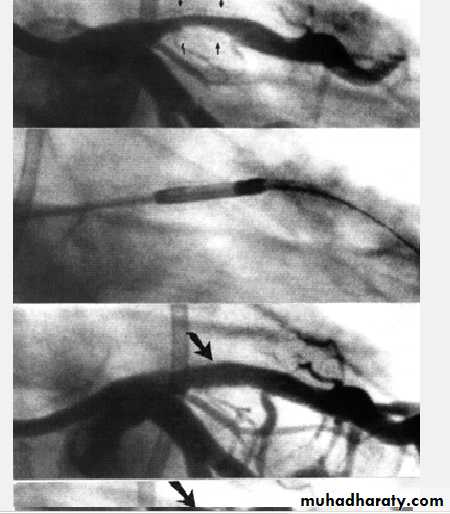

RevascularizationPercutanous C. Intervention (PCI) or C.A Bypass Grafting (CABG)

PCI which include Balloon Angioplasty + - Stenting Is indicated in discrete single vessel or two vessel lesions except that of the Proximal Left Anterior Descending artery LADCABG is for Left Main Stem lesion , Three Vessel Disease, and proximal LAD 1-2 vessels Disease

Benefits and drawbacks of PCI

PCI benefitsImproves symptoms only (no evidence it improve survival ) and used for stenosis of native CA or graft .

PCI drawbacks ( related to lesion morphology, operator skills, and co morbidity ( page 588 Davidson)

1- Dissection and or Thrombosis ( 2-5%) Usually corrected by stenting

2- Restenosis occur in up to 33% in Angioplasty and reduced by Stenting with Bare Metal Stent ( BMS ) and reduced further by using Drug Eluting Stents (DES). Restenosis still occur in 10%. Dual antiplatelets needed

3- Late stent thrombosis occur in 0.6 % every yr.